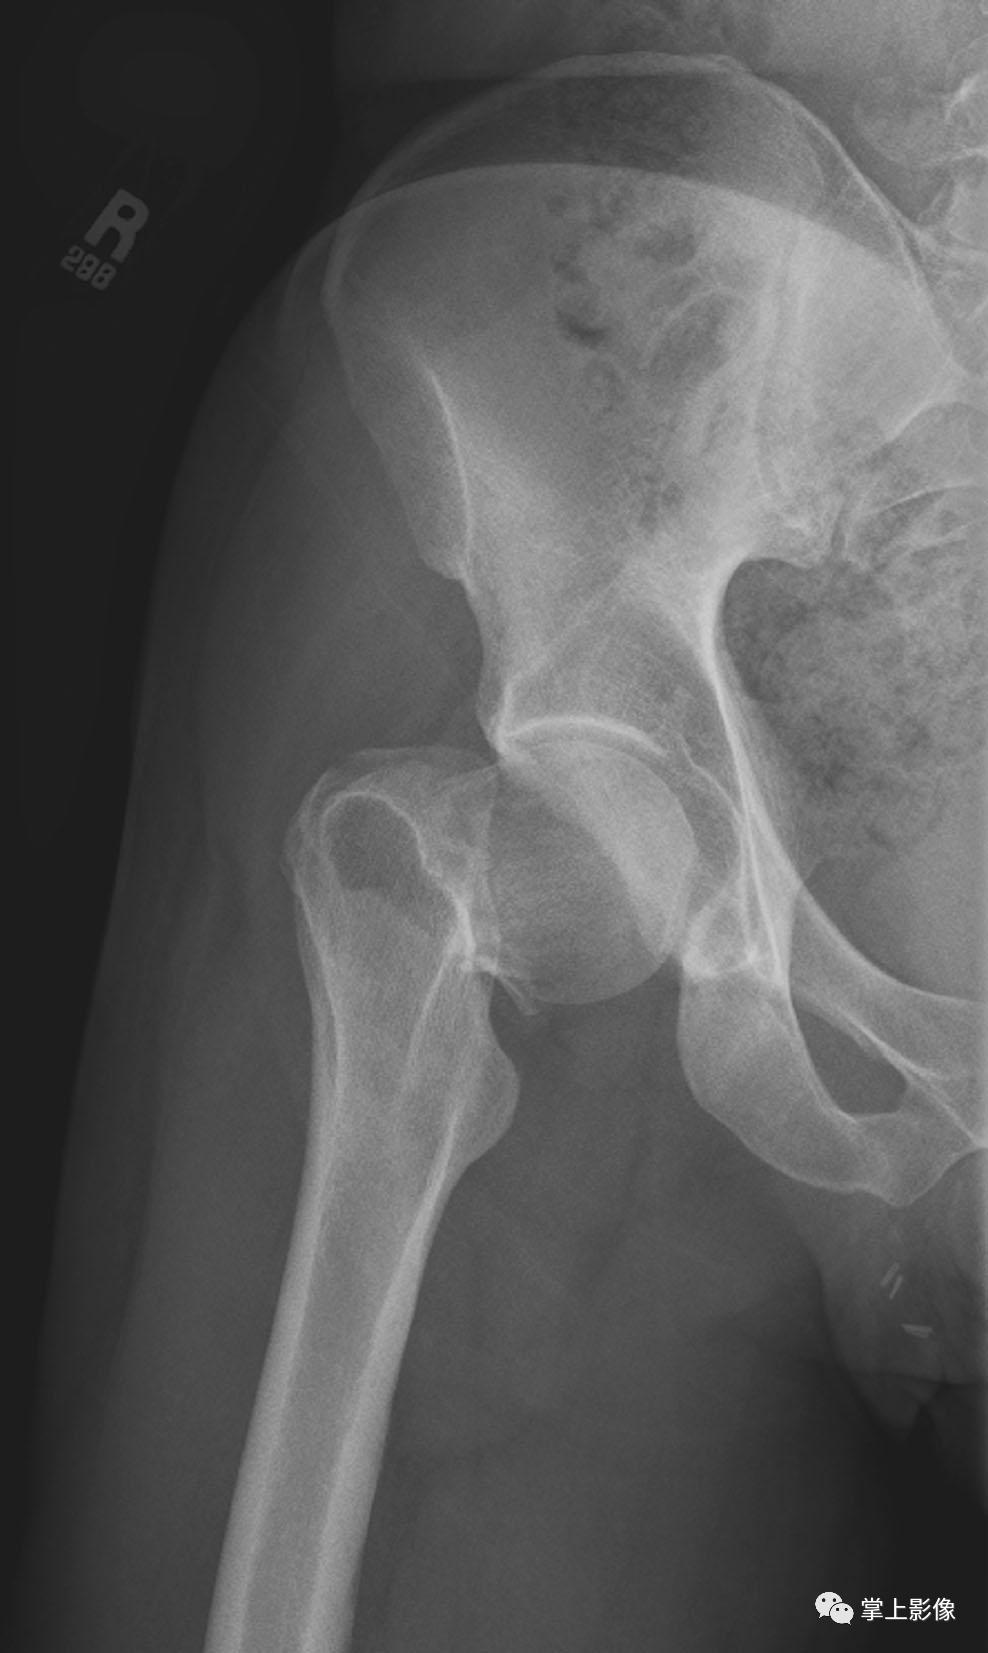

X线

- 患侧关节不同程度的关节肿胀、关节内积液

- 关节骨折,但所有隐匿性骨折均无法诊断

- 仅少数可直接显示液-液平(未采用水平投照、关节囊内血液及脂肪量太少、积血掩盖少量积脂),在某种程度上,通过关节囊内密度升高的情况可以疑诊为创伤性膝关节积脂血症,但也无法确诊